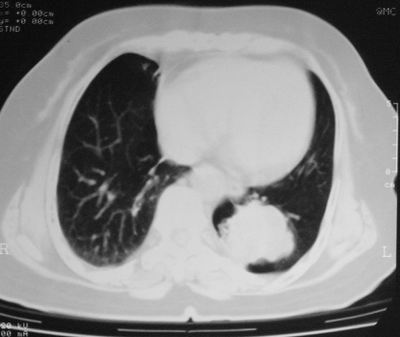

患者,女,64岁,4年前左腮腺"多形性"腺瘤手术治疗史.现复查胸部ct见左下肺块状影,该影与原左腮腺手术是否有联系?

本次复查胸部ct

左下肺软组织块影,有分叶、毛刺、空泡及胸膜牵拉征,左下肺周围性肺癌。

左肺下叶周围型肺癌,支持!(软组织肿块+分叶+毛刺+空泡+胸膜凹陷征)

左下肺软组织密度影,可见分叶,边缘可见毛刺征,胸膜增厚,强烈要求左下肺周围型肺癌

左下肺后基底段实性肿块,周围有毛刺,病变周围有肺气肿,与降主动脉间有条带状影相连,病灶4年前查体发现,纵隔内未见肿大淋巴结。考虑.肺隔离症,建议增强扫描与周围型肺癌鉴别。